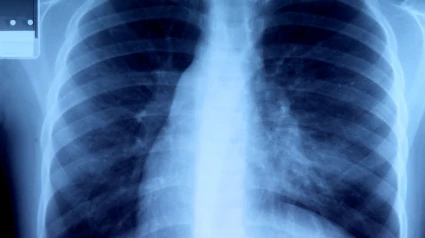

Un diagnóstico temprano y más afinado para cada paciente: la necesidad de atajar el cáncer de pulmón

Cerca de 32.700 casos. Esos son los que se diagnosticaron en nuestro país en 2024 de cáncer de pulmón, convirtiéndose este tipo, en el tercero más frecuente de nuestro país.

Es un tipo de cáncer, huelga decirlo, que se considera incluso “silencioso”, porque en muchos pacientes, los síntomas aparecen tarde o se confunden con otras patologías.

Cuando se trata de un cáncer como este, que puede ser “silencioso”, es necesario hacer un diagnóstico lo más temprano posible.